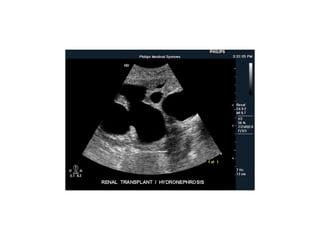

Hydronephrosis and hydroureter

Hydro nephrosis and hydro ureter